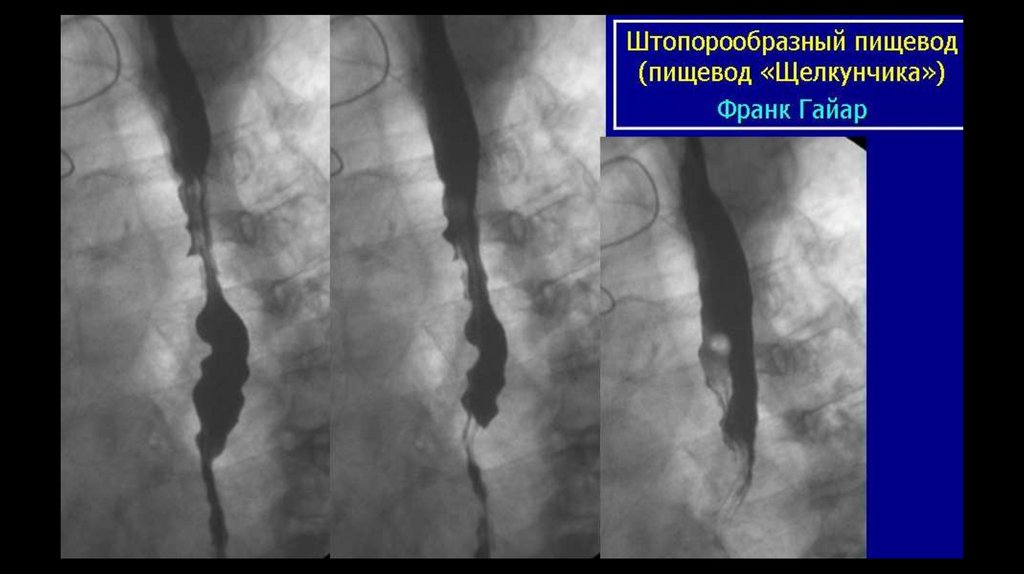

• «Пищевод щелкунчика» (синоним — сегментарный спазм пищевода) —

нарушение моторики пищевода, при котором наблюдаются сокращения

дистальной части пищевода высокой амплитуды и большой длительности.

Некоторые симптомы: дисфагия, сильная боль в груди. Заболевание может

протекать бессимптомно.

• «Пищевод щелкунчика» — доброкачественное, непрогрессирующее

заболевание, не приводящее к серьёзным осложнениям.